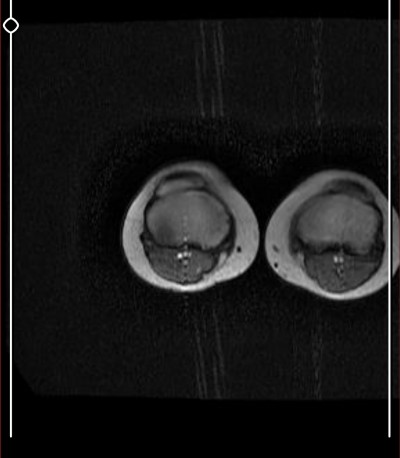

Kızlar çok önemli benim için aşırı şekilde dizlerim ağrıyor böyle çıktı

Mr sonucunu yazılı olarak birkaç güne alabilirsin tatlım biz bilemeyebiliriz sonuçta aramızda ortopedisyen yok  eşimdede sağlam bacakta tümör çıktı  3 cmlik o yüzden raporun çıkmasını bekle bence

Burada ortopedi hekimi yada radyoloji uzmanı yoksa bu görüntüleri kimse yorumlayamaz.Doktora sorulacak sorular bunlar